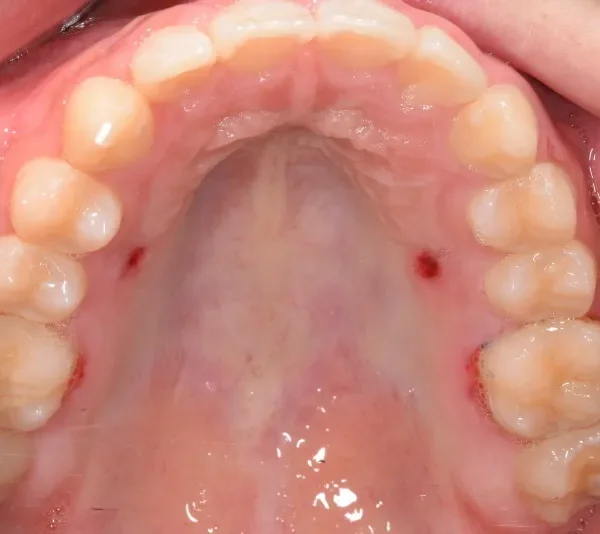

【子供の矯正(一期)】叢生・交叉咬合・前歯がゆがんでいる・8歳男児【S.N様】

初診時年齢 小学校3年生 (男性) 主訴 前歯がゆがんでいる・ガタガタ

診断名 叢生・交叉咬合 装置名

上下の幅が狭くガタガタに生えています。

乳歯があるうちはオリジナル矯正装置を使用しました。

初診